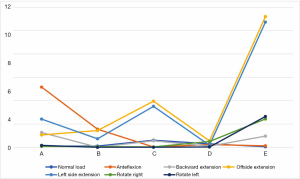

Under each working condition, as the defect volume increased, the stress differences between consecutive groups were as listed in Table 4.

Full table

We used the data to generate a dot plot to more intuitively show the relationship between the defect volume and the increase in stress (Figure 14).

The 5/5 defect in the anterior column of the injured vertebra was a simulated extreme condition that does not exist in actual clinical practice, so we removed this condition from consideration. According to the chart, after the implantation of the internal fixator, the stress increased significantly when the injured vertebra showed a defect. As the defect volume increased, the stress increased correspondingly, and the increase in stress represented by group D (stress difference between the 3/5 defect group and the 4/5 defect group) was the greatest.

When the removal of the internal fixator was simulated, the stress outcomes of the five types of superior endplate collapse (defect volumes of 1/5, 2/5, 3/5, 4/5, and 5/5 of the anterior-two-thirds edge of the vertebral body, respectively) under vertical load, anteroposterior flexion, lateral flexion, and left and right rotation conditions. The stress distribution maps are shown in Table 6. We also made a table of the stress difference between the two groups in Table 7 and generated a dot plot (Figure 15). It can be seen that with the removal of the internal fixator and the loss of support from the internal fixator as well as the increase in defect volume, the stress gradually grew larger. The dot plot of the difference between groups showed that as the stress increased, the magnitude of change in the combined stress represented by group C (stress difference between the 2/5 defect group and the 3/5 defect group) under the seven working conditions was the largest, suggesting that after the removal of the internal fixator from injured vertebrae with superior endplate collapse and bone defect, when the collapse defect area reached 3/5 of the anterior column of the vertebral body, the concentration of stress increased significantly. This suggests that the risk of continued compression or even refracture of the injured vertebra increases after the removal of the internal fixator.